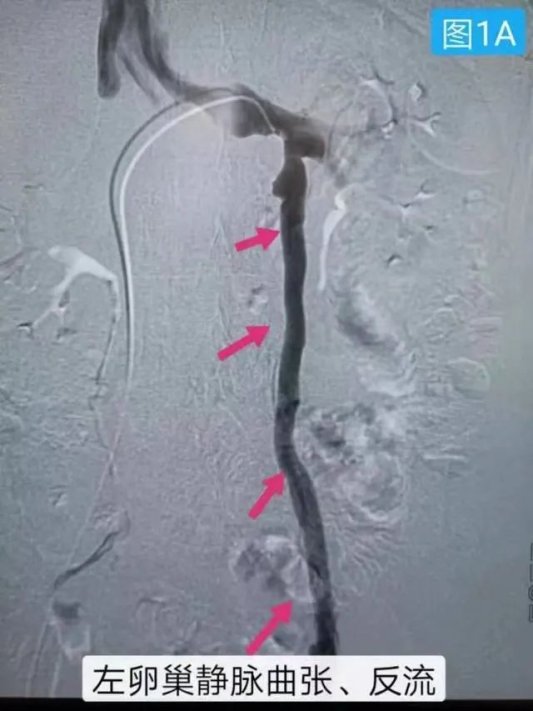

提示左侧卵巢静脉明显反流,主干明显增粗扩张,其属支明显增多增粗,盆腔淤血综合征诊断明确,并选择直径与卵巢静脉相同的弹簧圈及适量聚桂醇硬化剂彻底栓塞卵巢静脉,5分钟后再行卵巢静脉造影,卵巢静脉未显影栓塞成功。